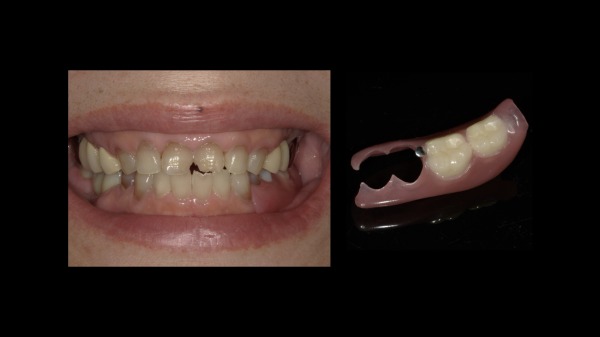

患者様は60代の女性の方です。当院にメンテナンスで通院しておられましたが、他院にて入れた左下の被せ物が虫歯で取れてしまいました。虫歯をしっかり削っていくと、ご自身の歯がほとんどなくなってしまい、被せ物を再度行うことが不可能となり、残念ながら抜歯となりました。

抜歯後のお口の状態がこちらになります。

こちらがノンクラスプデンチャーの写真になります。